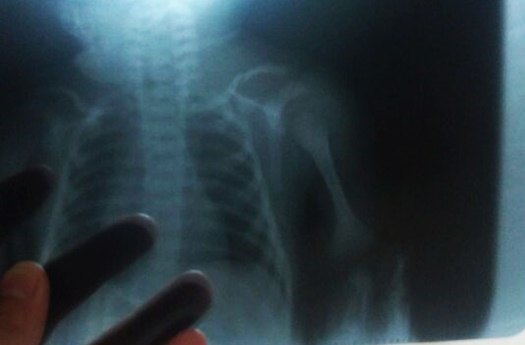

NEGLIGÊNCIA – Recém-nascido recebe alta com clavícula fraturada na maternidade municipal